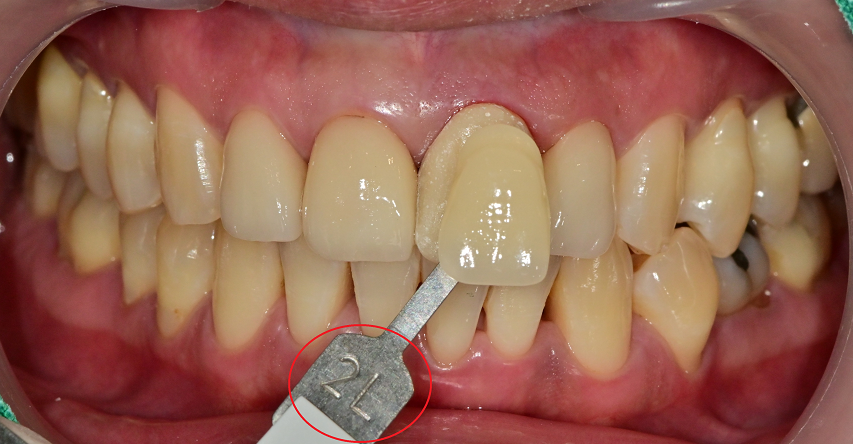

빨간색 동그라미는 치아의 색상을 카테고리화 시킨 것인데

shade guide란것을 이용하여 최대한

주변 치아와 맞는 색을 찾으려 노력을 해봤습니다.

미백에서도 쓰여지고, 심미적인 치료를 할 때는 자주 이용하는 도구입니다.